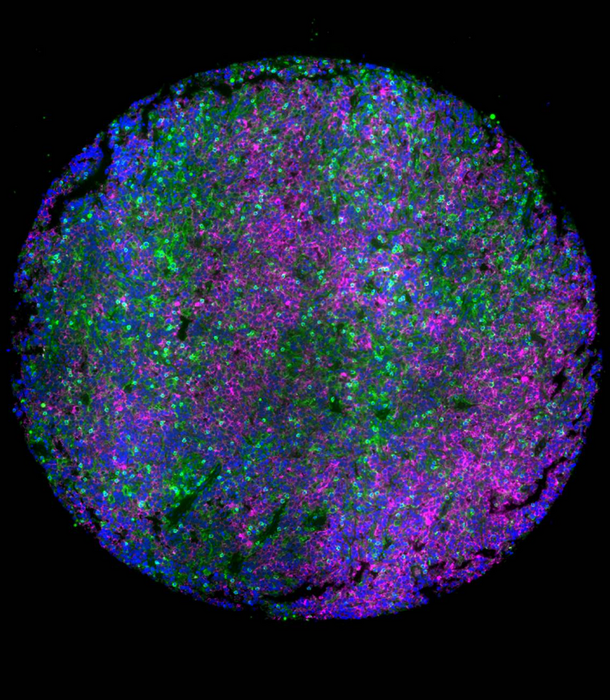

Lymph node tumor microenvironment of lymphomas with malignant B cells (magenta) surrounded by T cells (green), which induce survival mechanism in tumor cells and dampen the response to therapeutics. This microenvironment was faithfully mimicked in a 3D hydrogel of lymphoma patient tumors to discover role of tumor microenvironment in lymphomas and how combinatorial therapies can overcome resistance in tumors. Blue: Nucleus. Credit: Mayar Allam, Ahmet Coskun, and Ankur Singh (Georgia Institute of Technology)